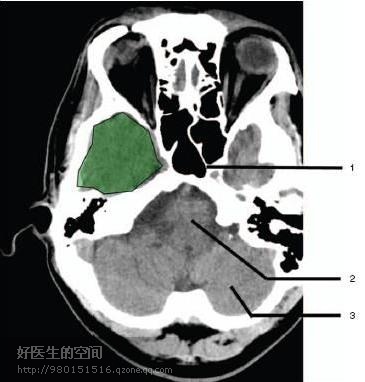

1、蝶窦(Sphenoid sinus) 2、延髓 (Medulla oblongata) 3、小脑 (cerebellum)

绿色部分为颞叶(Temporal Lobe),